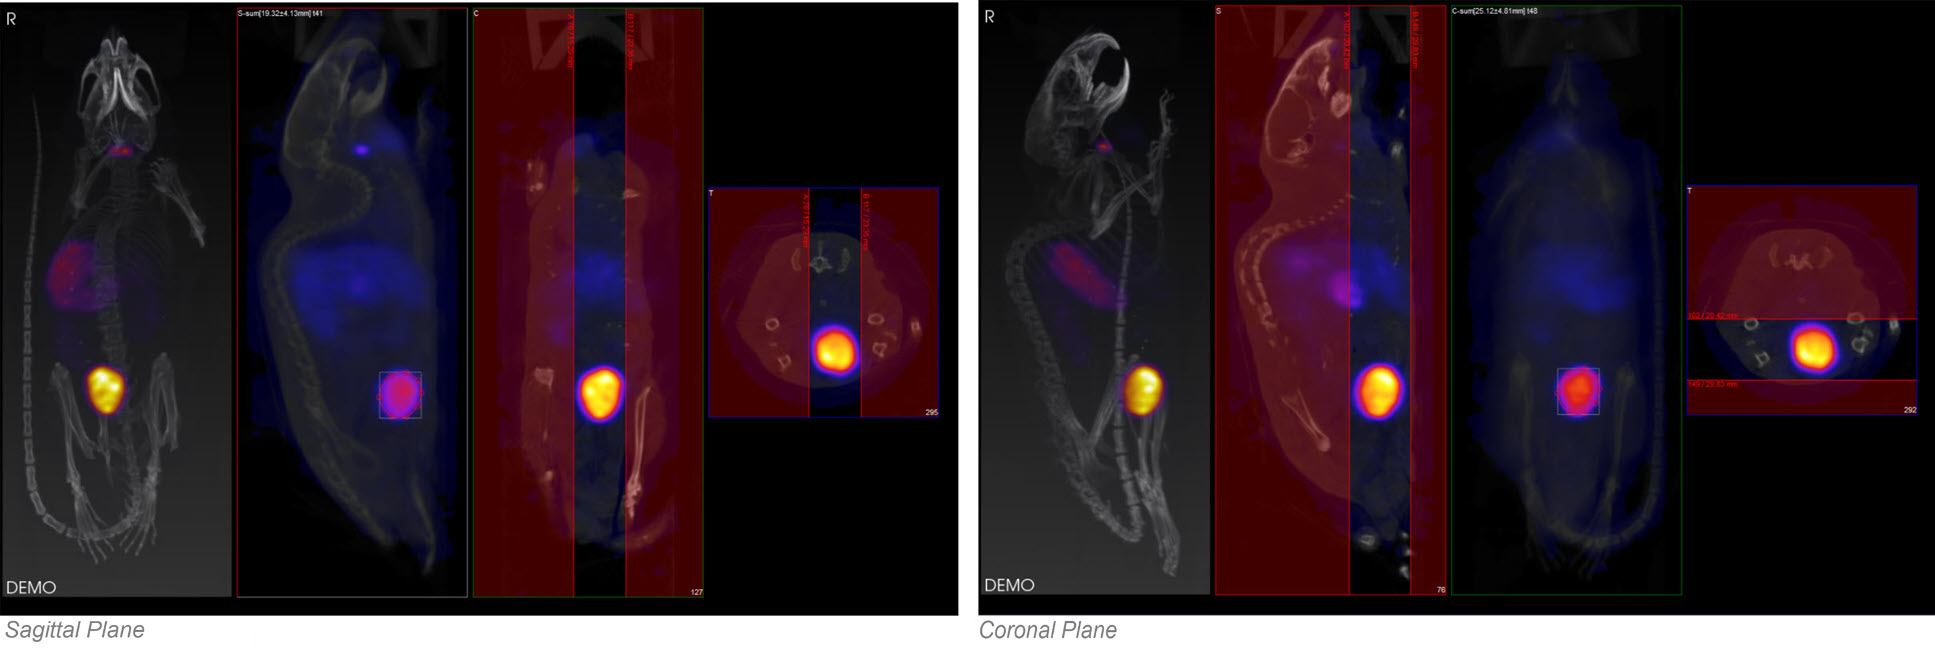

The ROI may be drawn in either the transverse (default), coronal, or sagittal plane. To toggle between these options, use the View menu in the Operator tab of the main menu.

By using the View menu, it is also possible to draw ROI boundaries in the sagittal plane or coronal plane: